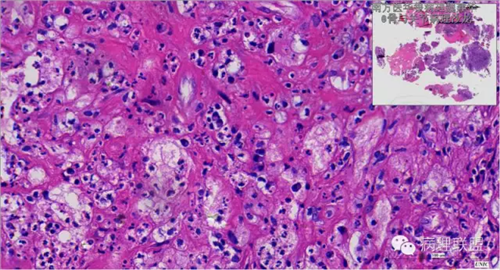

来源于组织细胞的相似性骨病ECD vs RDD 看图说话